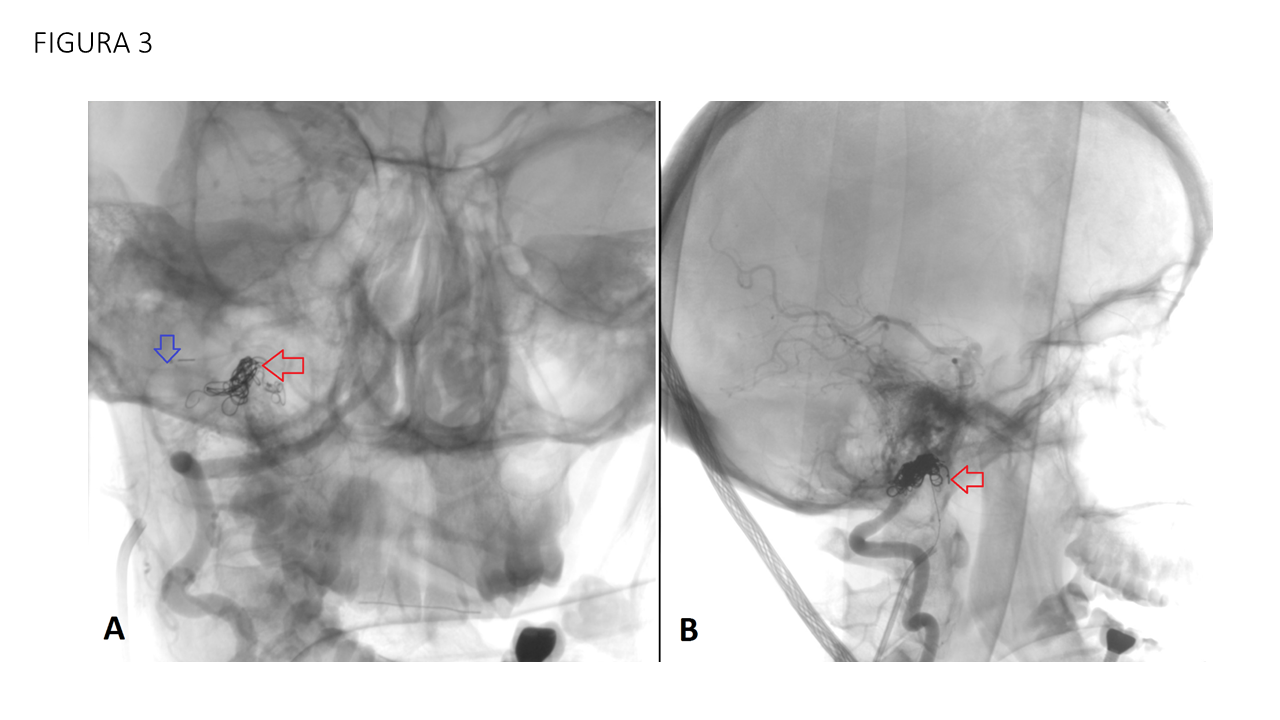

FIGURA 3 Proyecciones AP (A) y lateral (B) angiográficas. Se realiza abordaje yugular derecho cateterizando supra selectivamente la vena condílea derecha y posicionando el microcatéter en el pouch venoso de drenaje de la fístula (flecha azul). Se procede a la liberación de múltiples coils (flecha roja).